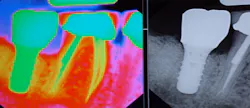

Let’s first start by comparing the shapes of a natural tooth and an implant. Natural teeth have a wider neck while dental implants have a smaller neck. The difference in design will be more apparent in molar teeth because molars have multiple roots and dental implants replace the roots of any tooth with only one root or fixture. Since implants have a smaller circumference at the neck of the crown (figure 1), the patient may experience the feeling of a wider space when using interproximal cleaners. This is to be expected with dental implants; however, patients who have a single implant next to natural teeth have an increased risk for caries on the opposing natural teeth if proper home-care techniques are not established. This often occurs because the bone height around natural teeth is higher than the proximal implant and requires more thorough cleaning by the patient. (3) Thus, it is imperative for preventative specialists to physically demonstrate to their patients all of the tools and techniques that will help establish a home care regime that is simple, effective and most importantly, achievable!

Figure 1: Implant vs. natural tooth circumference in a molar. Image courtesy Daniel Orellana, DDS.